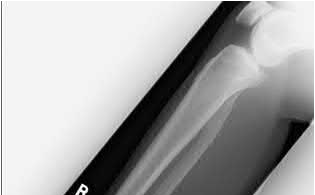

A 35-year-old-male sustains the fracture seen in Figure A. Which of the following reduction forces must be applied to the proximal fragment to correct the deformity commonly seen in these fractures?

Figure A demonstrates a displaced subtrochanteric femur fracture with an intact lesser trochanter. The pull of iliopsoas on the lesser trochanter as well as the intact external rotators and gluteal musculature results in the the proximal fragment being in a flexed and externally rotated or abducted position (the most common post operative deformity). Reduction manuevers must be biologically friendly but also counteract the flexion/abduction moment. Lundy's review article discusses evaluation and treatment of subtrochanteric fractures. The review article details the various implants often used which include 95 degrees plates, femoral reconstruction nails, or trochanteric femoral nails with interlocking options. Lundy's article discourages the use of the 135 degree screw and side plate combo due to high failure rates in these fracture patterns. Bedi et al also review treatment of these fractures and discuss common

problems of malunion, nonunion, and implant failure. The article reviews reduction techniques that are soft tissue friendly, as well as the use of appropriate implants in these fracture types.